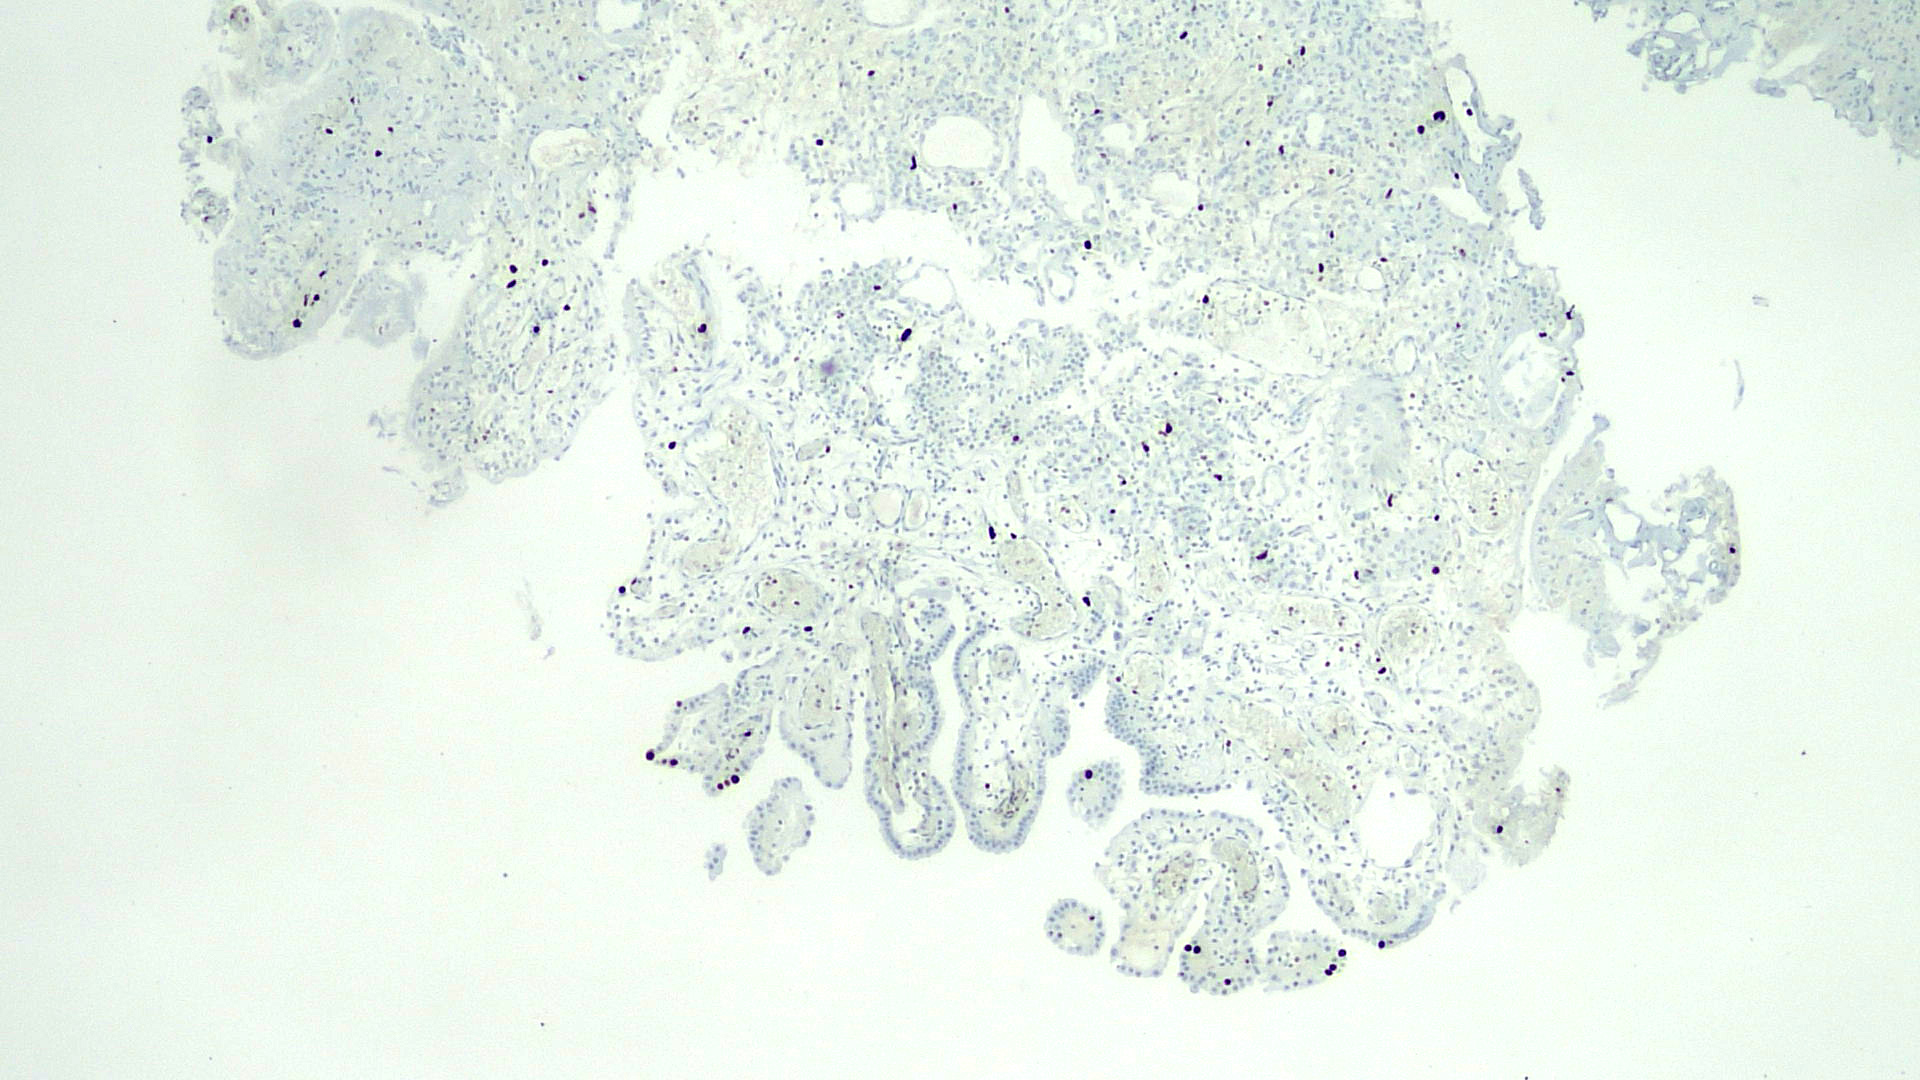

- PAX2, PAX8, AMACR, CD10, CK7 (Am J Surg Pathol 2014;38:1664)

- CK903, EMA, S100A1 (Ann Diagn Pathol 2013;17:41)

- Napsin A (Hum Pathol 2020;102:23)

- Weakly positive or negative for PSA and PSAP

Negative stains

- p63, CEA (Virchows Arch 2013;463:819)

- GATA3 (positive in 40% of cases) (Am J Surg Pathol 2014;38:1664)

- Very low Ki67 proliferation rate (< 5%) (Ann Diagn Pathol 2019;38:11)